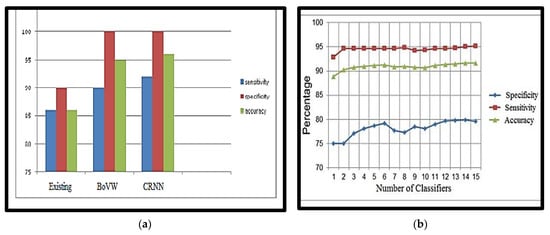

The obtained accuracy after optimisation was 98.5%. Table 6 analyses performance parameters for the BoVW and CRNN classifiers. The parameters considered here are accuracy, sensitivity, specificity, precision, PSNR and MSE values. For the BoVW classifier, accuracy was 96.5%, sensitivity was 93%, specificity was 100%, precision was 93.5%, PSNR value was 42.278, and the MSE was 3.474. For the CRNN classifier, accuracy was 98.5%, sensitivity was 95%, specificity was 100%, precision was 95.5%, PSNR was 69.154, and the MSE was 2.193. From Table 6, it is clear that CRNN provided the best output performance in terms of accuracy and precision. Table 7 shows the error and accuracy comparison regarding different classifiers. Figure 15 shows (a) the Performance Measure of the classifier and (b) the Performance Graph of the classifier.

(a) Performance Measure of the classifier, (b) Performance Graph of the classifier.

Compared to other methods, the proposed nano-based CRNN classifier provides 98.5% accuracy, which is greater than other techniques (Table 8). The proposed technique effectively smooths the image and accurately determines the minute nodules. Finally, the technique accurately classifies the image, whether benign or malignant.